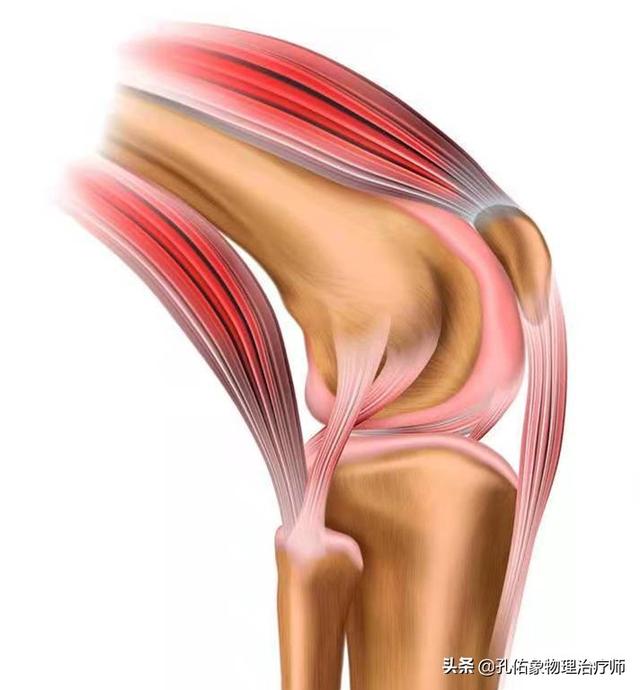

In unserem Kniegelenk gibt es zwei Menisken auf der medialen und lateralen Seite, der mediale Meniskus ist mit dem medialen Seitenband und der medialen Gelenkkapsel verbunden, während der laterale Meniskus mit der lateralen Gelenkkapsel verbunden ist, und der Quadrizeps, der Semimembranosus-Muskel und der Popliteus-Muskel auf der Rückseite sind ebenfalls mit dem Meniskus verbunden. Der Meniskus ist eine sehr wichtige Struktur in unserem Körper, die nicht nur die Tiefe der Gelenkgrube vergrößert, die Verbindung zwischen Oberschenkel- und Wadenbeinknochen anpassungsfähiger macht und die Stabilität des Kniegelenks erhöht, sondern gleichzeitig auch das Kniegelenk schützt und als Stoßdämpfer fungiert.

Im täglichen Leben ist jedoch dieDer Meniskus wird oft übersehen, aber Knieschmerzen hängen auf die eine oder andere Weise mit ihm zusammen!. Um ihn besser kennen zu lernen, ist es auch notwendig, die Nährstoffversorgung des Meniskus zu kennen:

Der Meniskus stützt sich stark aufBlut和Synovialflüssigkeit in der Gelenkkapsel (Medizin)Der Meniskus wird im Wesentlichen von zwei Substanzen versorgt: Das äußere 1/3 des Meniskus ist durchblutet und hat einen kleinen Anteil in der Mitte, während das innere 1/3 nicht durchblutet ist und hauptsächlich von der Synovialflüssigkeit der Gelenkkapsel ernährt wird.

Wenn der Meniskus degeneriert ist, kann der Meniskus beschädigt werden, wenn Sie unbeabsichtigt in die Hocke gehen oder aufstehen und Ihren Körper verdrehen. Offensichtlich tragen Probleme mit der Blutversorgung, der Dämpfung und der Synovialflüssigkeit direkt zu Kälte, Schmerzen und Rasseln bei, die Sie bei Bewegungen verspüren.